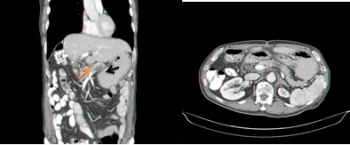

- טומוגרפיה ממוחשבת (CT) : בטומוגפיה ממוחשבת אפשר לראות היטב את הלבלב והנגעים בו פחות טוב נראה את מערכת הצינורות (תצלום 28.9)

בכל הבדיקות האלו נראה הרחבה של צינור הלבלב הראשי או באחד הענפים שלו. במקרים מסוימים שאיבה במחט עדינה (FNA) תאשר את האבחנה.